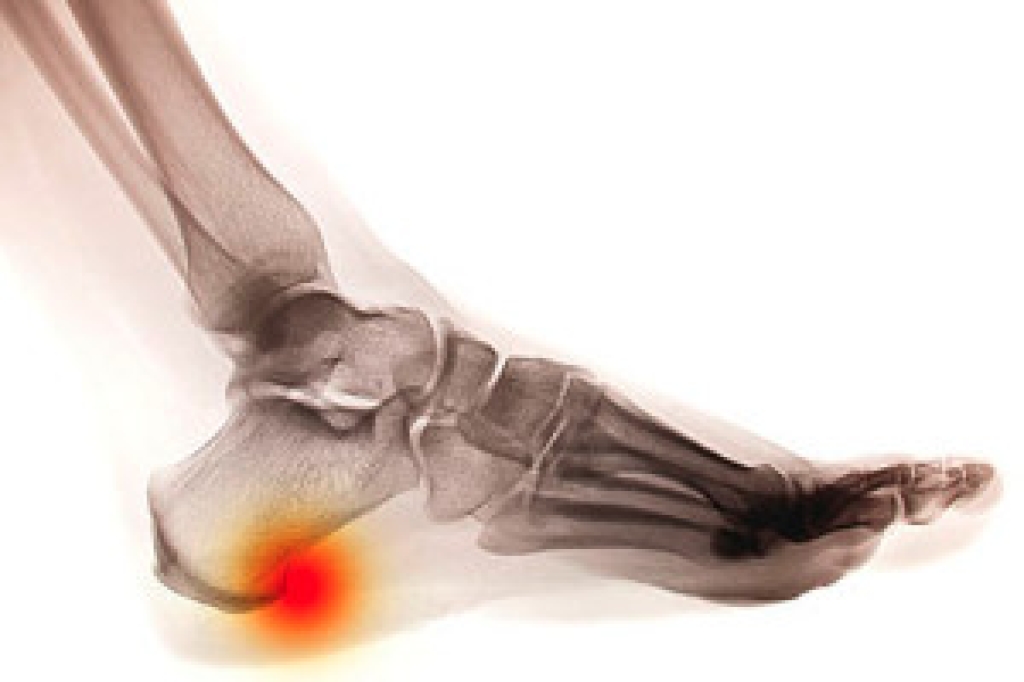

In order to diagnose your bunion, your podiatrist may ask about your medical history, symptoms, and general health. Your doctor might also order an x-ray to take a closer look at your feet. Nonsurgical treatment options include orthotics, padding, icing, changes in footwear, and medication. If nonsurgical treatments don’t alleviate your bunion pain, surgery may be necessary.